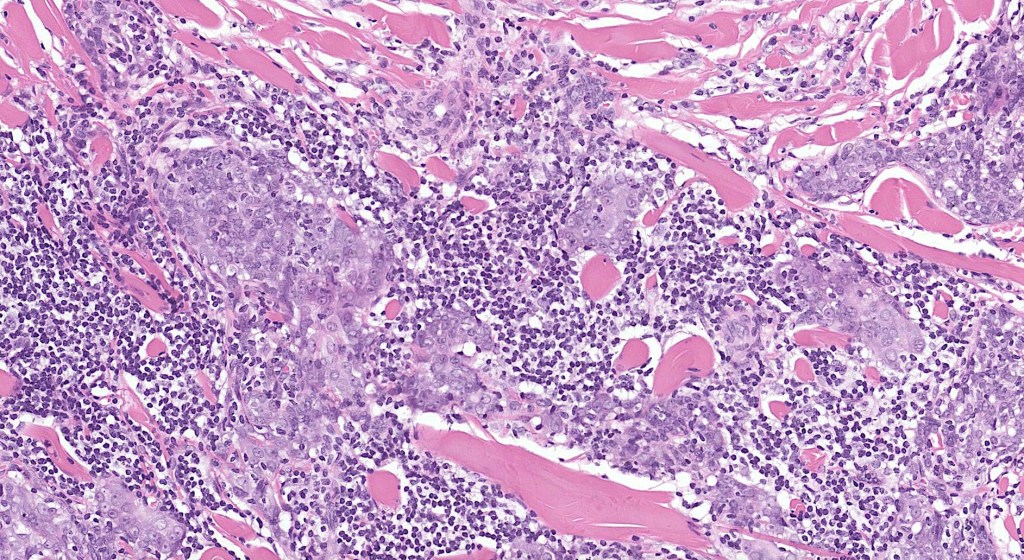

•Dermal generally circumscribed tumor nodule (less often it may show an infiltrative border)

•Syncytial epithelial component in nests, cords or sheets surrounded by an intense lymphoplasmacytic infiltrate

•Epithelial cells are large with abundant cytoplasm and vesicular nuclei with conspicuous nucleoli

•Marked mitotic activity, variable pleomorphism

•Absence of an epidermal connection